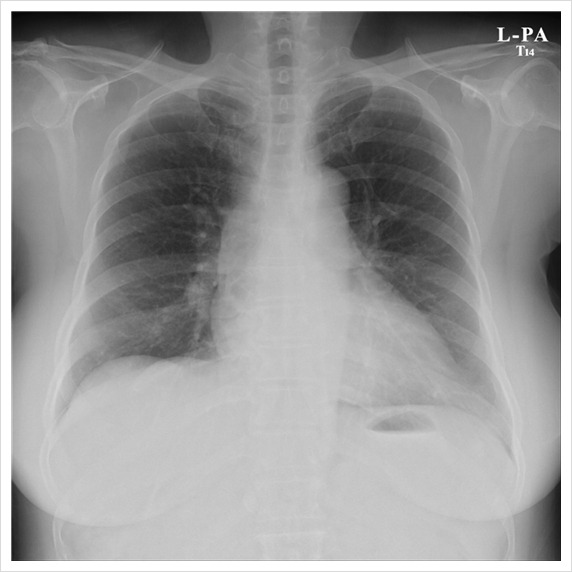

Order가 Chest AP로 나와서 Worklist에서 AP로 setting을 불러왔어요...

하지만 환자 상태가 양호하여 서서 촬영을 했는데

FCR-Velosity에서 이런식으로 image를 만들어주네요 .....

무슨 Rib도 아니고....-_-

그래서 setting값을 바꿔서 보내주었어요.

Chest PA사진 보세요.

영상의 차이가 확~ 나시나요???

미세한 Lung Image의 차이... 가끔 실수로 넘기게 되는 경우가 있는데